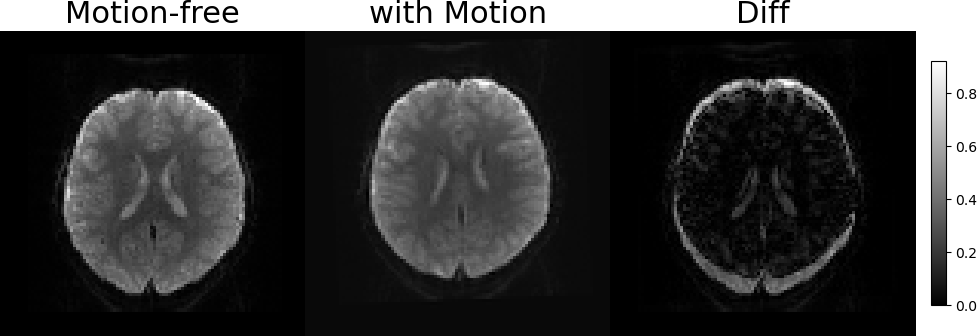

3.2 Representations of Transformations and Slices Generation

Figure 3: Illustration of the SVR problem. Two examples of free-motion volumes and volumes with synthetic motion. From left to right: Coronal LABEL:sub@fig1:a,LABEL:sub@fig1:b and Sagittal LABEL:sub@fig1:c,LABEL:sub@fig1:d views of the free-motion volumes, the generated volumes after applying the rigid transformations and sampling the slices, and the pixel-wise MSE between them, respectively. The artifacts due to the slice-level motion are visible in both Sagittal and Coronal views, however, they are not dipicted in the axial (imaging) axis of the image LABEL:sub@fig1:e,LABEL:sub@fig1:f.